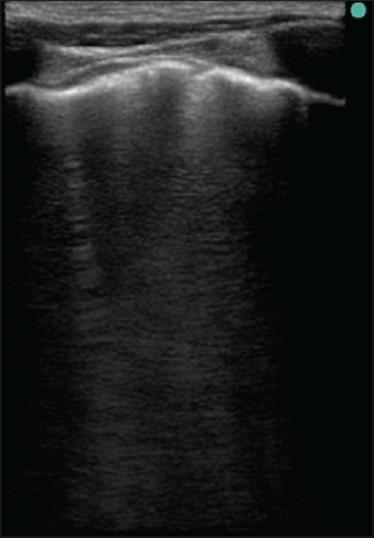

Several studies have shown that the number of B-lines was related to the amount of extravascular lung water (EVLW). In our study, we aimed to demonstrate the magnitude of the incremental B-lines in shock patients with positive net fluid balance and the association with gas exchange impairment.

We performed trans-thoracic ultrasound at admission (T0) and at follow-up period (TFL) to demonstrate the change of B lines (ΔB-lines) after fluid therapy. We compared the total B-line score (TBS) at T0 and TFL and calculated the Pearson's correlation coefficient between the ΔB-lines and PaO2/FiO2 ratio.

A total of 20 patients were analyzed. All patients had septic shock. Net fluid balance was + 2228.05 ± 1982.15 ml. The TBS at T0 and TFL were 36.6 ± 23.73 and 63.80 ± 29.25 (P < 0.01). The ΔB-lines along anterior axillary line (AAL) correlated to the ΔTBS (r = 0.90, P < 0.01). The ΔB-lines along AAL had inverse correlation to PaO2/FiO2 ratio (r = -0.704, P < 0.05). The increase of B-lines ≥ 10 was related to the decrease of PaO2/FiO2 ratio. The inter-observer reliability between two ultrasound readers was high (r = 0.92, P < 0.01).

The number of B-lines increased in shock patients with positive net fluid balance and correlated to impaired oxygenation. These data supported the benefit of ultrasound for assessing the EVLW.